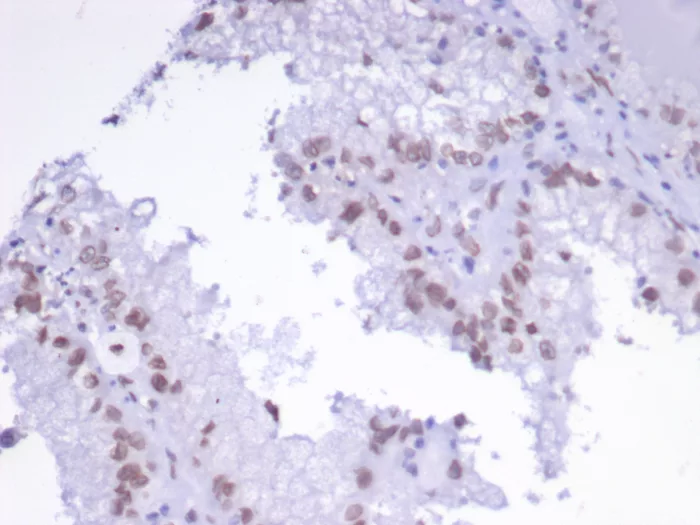

Formalin-fixed, paraffin-embedded human renal cell carcinoma stained with TFAP2A Mouse Monoclonal Antibody (PCRP-TFAP2A-2C2). HIER: Tris/EDTA, pH9.0, 45min. 2°: HRP-polymer, 30min. DAB, 5min.